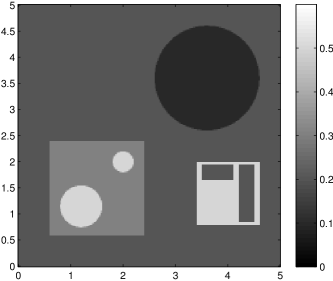

The data (see Figures 1 and 2) was generated in the diffusion model (1.2) using self-written (linear-basis) finite element code in MATLAB. For both examples, we took and used a uniform boundary condition . The simulated data were generated on a -grid and then down-sampled (by averaging) to to avoid inverse crime. After that, Gaussian noise with different intensities (standard deviations of and of the average signal value ) was added to the data.

Reconstruction results and error profiles at different noise levels can be seen in Figures 3 and 4. In both examples, the noise-free reconstructions are very accurate and contain mostly smoothing error. In the low-noise reconstructions, due to the fact that more regularization is necessary, some of the parameter variation is underestimated. In the high-noise examples, most detail in is lost since a lot of regularization is required to get reasonable results. The fine detail in can, however, still be recovered very accurately in both examples.